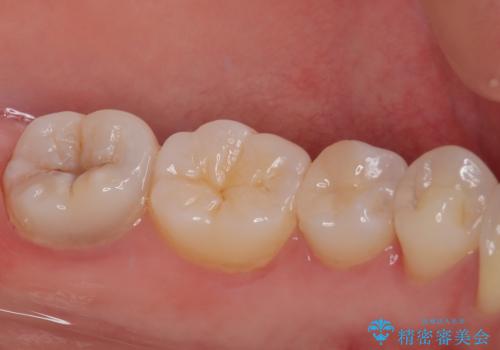

左下に虫歯が見つかった セラミックインレー修復

- 虫歯ができた気がするとのことで来院された患者様です。検査後セラミックインレーにて修復治療を行っていくことになりました。

拡大鏡視野下で虫歯の除去を行い、セラミックインレーに適した形に整えました。

歯と歯茎の間に圧排糸と言われる糸を入れてシリコーン印象材にて精密な型どりをしました。

セラミックインレーの装着時には、唾液の侵入を防ぐために、ラバーダム防湿を行いました。

見た目、機能面共に大変喜んでいただきました。

歯と歯の間の虫歯をコンポジットレジンや保険のメタルインレーで治すと段差ができたりして清掃性が悪くなるので、セラミックインレー修復やゴールドインレー修復などの適合の良い詰め物で治療することをオススメします。